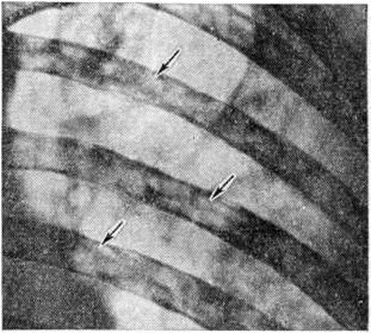

Рентгенологическое исследование костей скелета (грудной клетки, таза, черепа, плечевой и бедренной кости, позвоночника) позволяет обнаружить в них очаги резорбции костной ткани и остеопороза. Про это следует помнить, что специфических рентгенологических признаков, характерных для миеломной болезни, не существует. Отсутствие остеодеструкций не исключает заболевания, а их наличие считается недостаточной для подтверждения диагноза.

Повреждения ребер при миеломной болезни